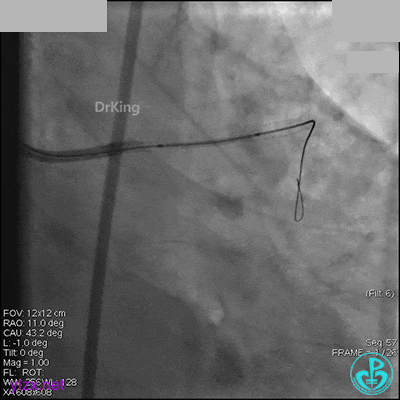

右冠脉中段充分扩张后欲植入3.5×38mm支架时,支架难以通过中远段扭曲处,且指引导管、导丝弹出飞扬。反复尝试导丝重新到达右冠脉远端时通过不顺利,局部造影剂滞留,远端血流接近3级。

右冠脉血流3级,患者无症状,终止手术。

1周后再次上台,右冠脉3级血流,3段局限性严重狭窄,内膜模糊,应该是上次操作夹层遗留下的血肿。